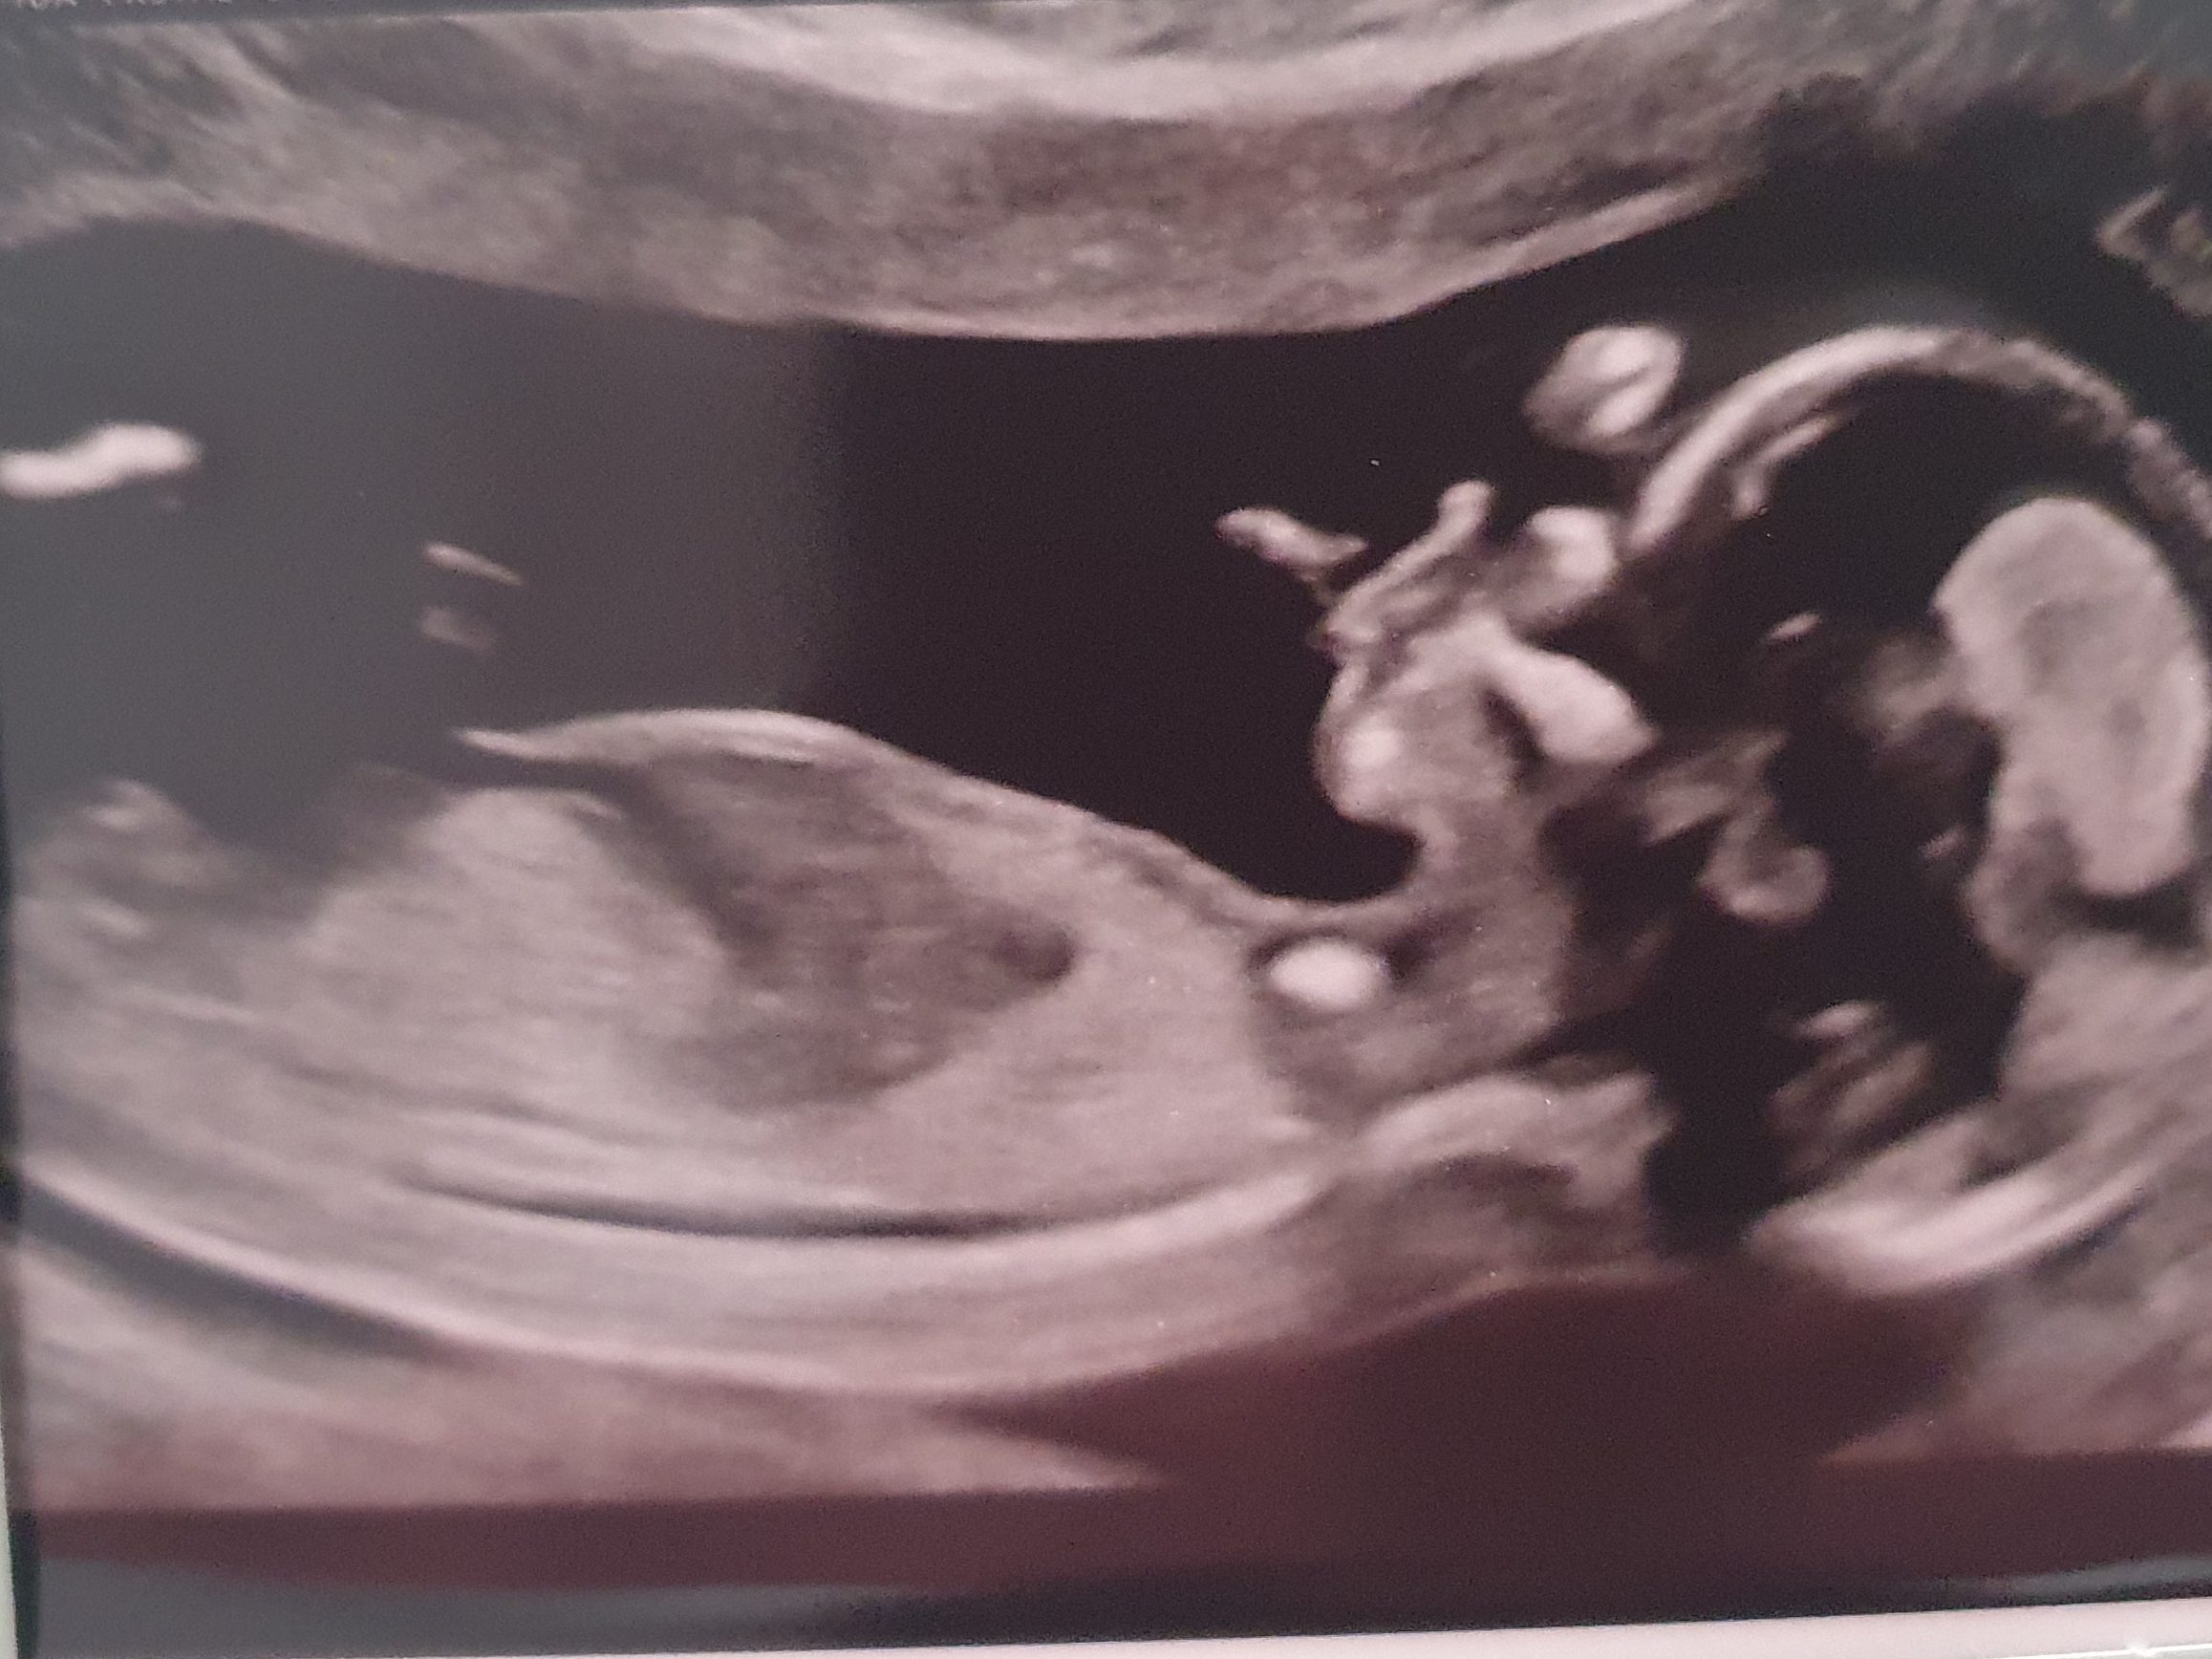

Finally, the day came for our 14 week scan. This scan is held between week 10 and week 14, and is usually referred to as the 12 week scan. Our was week 14 because the unit was fully booked. Finally, it was time for a belly scan – hurray!

We headed to the local hospital and over to the X-ray unit. It took quite a while to get the measurements to confirm the babies age, as it wriggled all over the place. One minute it was facing us, then it turned its back, then upside down.

The picture was amazingly clear as we saw the baby reach it’s hands up to its face, and seem to gesticulate at the world. A proper, moving, wriggling, little baby.